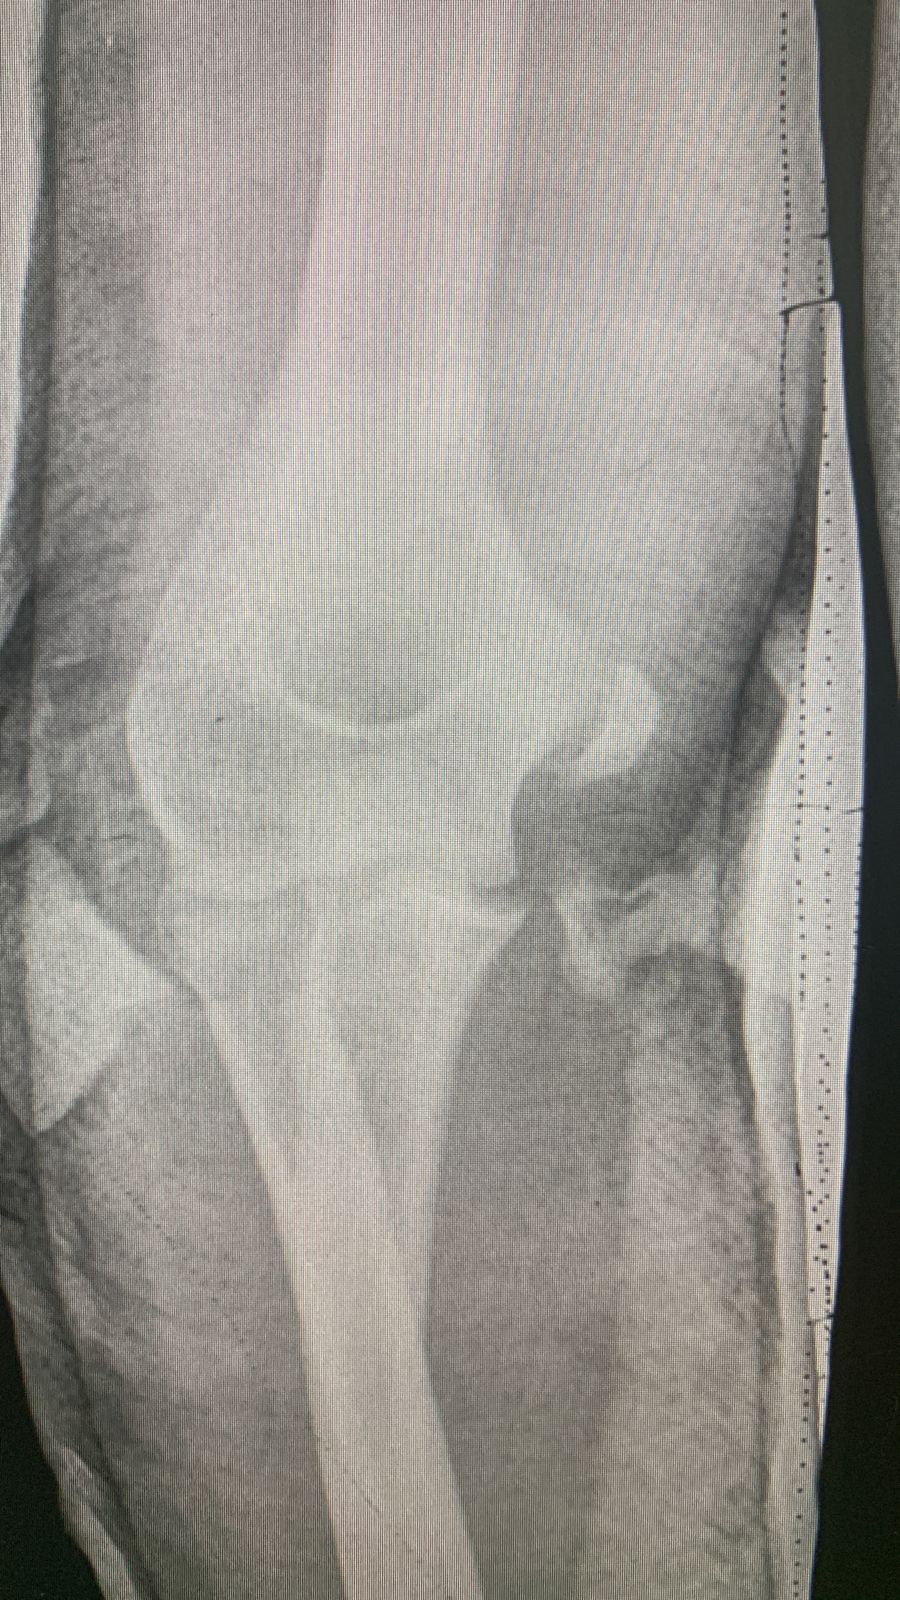

Перелом надмыщелка

Месяц назад сломал вроде как медиальный надмыщелок,отходил в гипсе 1 месяц и неделю.

По итогу один врач говорит,что кость не срастается,но снял гипс.При всем при этом сказал,чтобы я разрабатывал руку и если за 2 месяца она не срастётся,то придётся убирать обломок.Другой же врач говорит,что туда не надо лезть,все должно зажить и также посоветовал разрабатывать.Кому верить и что делать?

• Кликните для загрузки файла IMG-20220717-WA0006.jpg